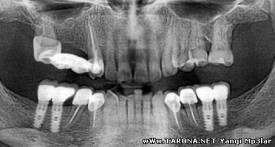

Стоматология соҳасида рақамли 3D технологиясидан  фойдаланиш ясама тишлар сифатини оширади ва вақтни анча тежайди, дея фикр билдиришди олимлар.

Гап шундаки тишларни протезлаш бемордан кўп вақт талаб қиладиган жараён. Бунда бемор бир неча бор клиникага ташриф буюриб, тишларининг ўлчамларини тўғрилигини текшириши керак бўлади. Кўпчилик учун эса бу бироз ноқулайлик туғдиради.

Рақамли 3D-модули эса протезлаш жараёнини тезлаштиради. Бунда тишларга гипсдан қолиб кийдирилиб ўлчам олиш ўрнига, шифокор махсус камера орқали беморнинг оғиз бўшлиғидан нусха кўчириб олади. Мазкур маълумотлар компьютерда сақланиб, оғиз бўшлиғининг тиш қўйиладиган жойлари уч карра катталаштирилган ҳолда намоён бўлади. Ана шу маълумотлар асосида шифокор беморнинг олдида тиш протезини тайёрлаши мумкин бўлади.

Маълумотлар махсус мосламага узатилиб, 10-20 дақиқа ичида тишларингиз тайёр бўлиши мумкин. Натижада эса шу қадар аниқ ишланган маҳсулот олинадики, бемор ўз тиши ва ясама тиш орасида ҳеч қандай фарқни сезмайди. Бундай натижага гипс қолиб орқали эришиш учун биринчидан кўп вақт талаб қилинади, иккинчидан тайёр бўлган маҳсулот барибир сифати бу қадар юқори бўлмайди.